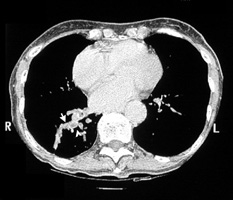

Bronchiectasis

Dilated bronchi with peribronchial fibrosis, visualized in various cuts of CT as cystic spaces, tubular shadows and branching densities.